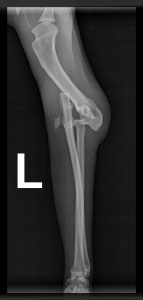

Nach vier Tagen war die Zeit der Ungewissheit für Luckis Besitzer endlich vorbei. Der Kater lebte, maunzte aber vor Schmerzen, nachdem er auf einmal wieder humpelnd im Garten aufgetaucht war. Vermutlich hatte das Tier einen Autounfall gehabt, denn im Röntgenbild erkannte der Tierarzt eine Ellbogenluxation. Versuche, das Gelenk wieder einzurenken, schlugen fehl. Zu alt war die Verletzung, die Schäden waren bereits zu groß, es drohte eine Amputation. Doch unserem Chefchirurg Dr. Klaus Zahn gelang das Kunststück, in einer diffizilen OP den Ellbogen mit einer Drahtzug-Gurtung wieder in der richtigen Position zu fixieren. Dadurch besteht Hoffnung, dass der Kater (im Foto mit Stationsärztin Lara Ißl) in ein paar Wochen sein Bein wieder voll belasten kann. Sofern Tier und Halter einige Regeln befolgen: sechs Wochen Zimmerhaltung, keine Sprünge, viel Physiotherapie. Um die Genesung ihres Lieblings zu unterstützen, haben die Halter daher eine geplante Flugreise storniert und freuen sich, dass Lucki bereits von Tag zu Tag besser läuft.